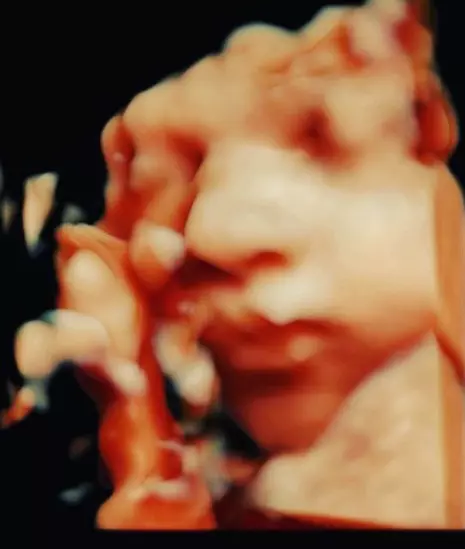

Cum arată Corina Caciuc, iubita lui Laurențiu Reghecampf, cu doar câteva săptămâni înainte să nască. A ieșit pe stradă în colanți!